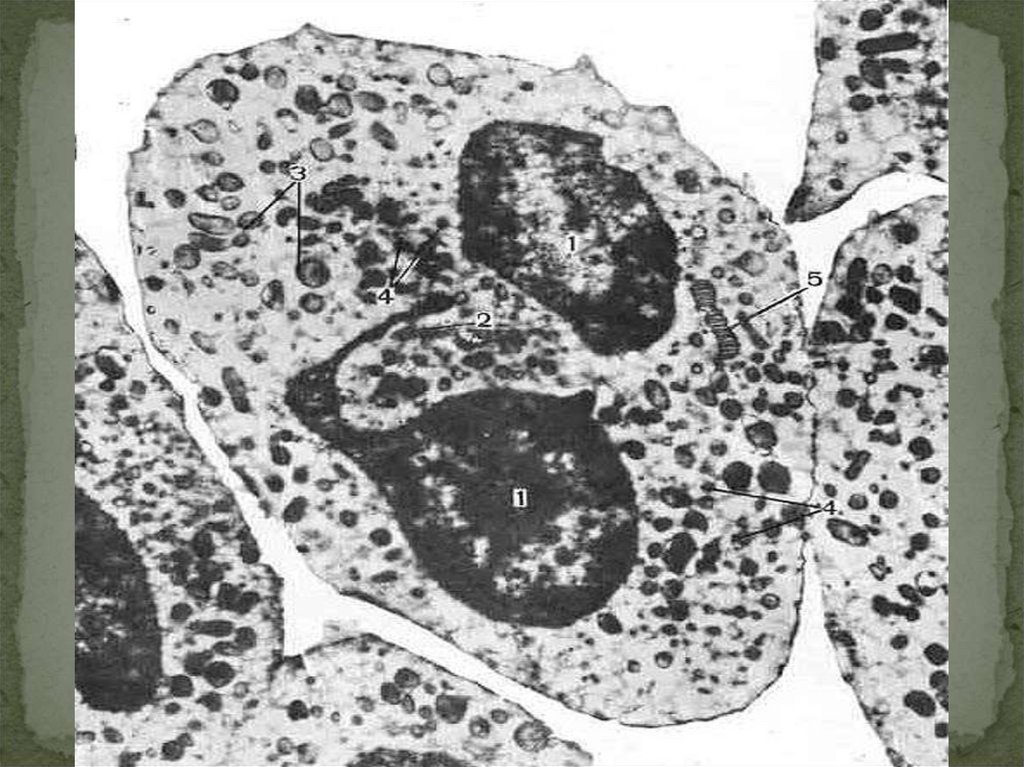

16. ЛЕЙКОЦИТЫ - ИСТИННЫЕ КЛЕТКИ КРОВИ

ЛЕЙКОЦИТЫ

В МАЗКЕ КРОВИ

НЕЙТРОФИЛЬНЫЙ ГРАНУЛОЦИТ

специализированные

лизосомы-пероксидаза,

лизоцим

лизоцим,

щелочную фосфатазу,

лактоферрин, коллагеназу

хемотаксис нейтрофилов